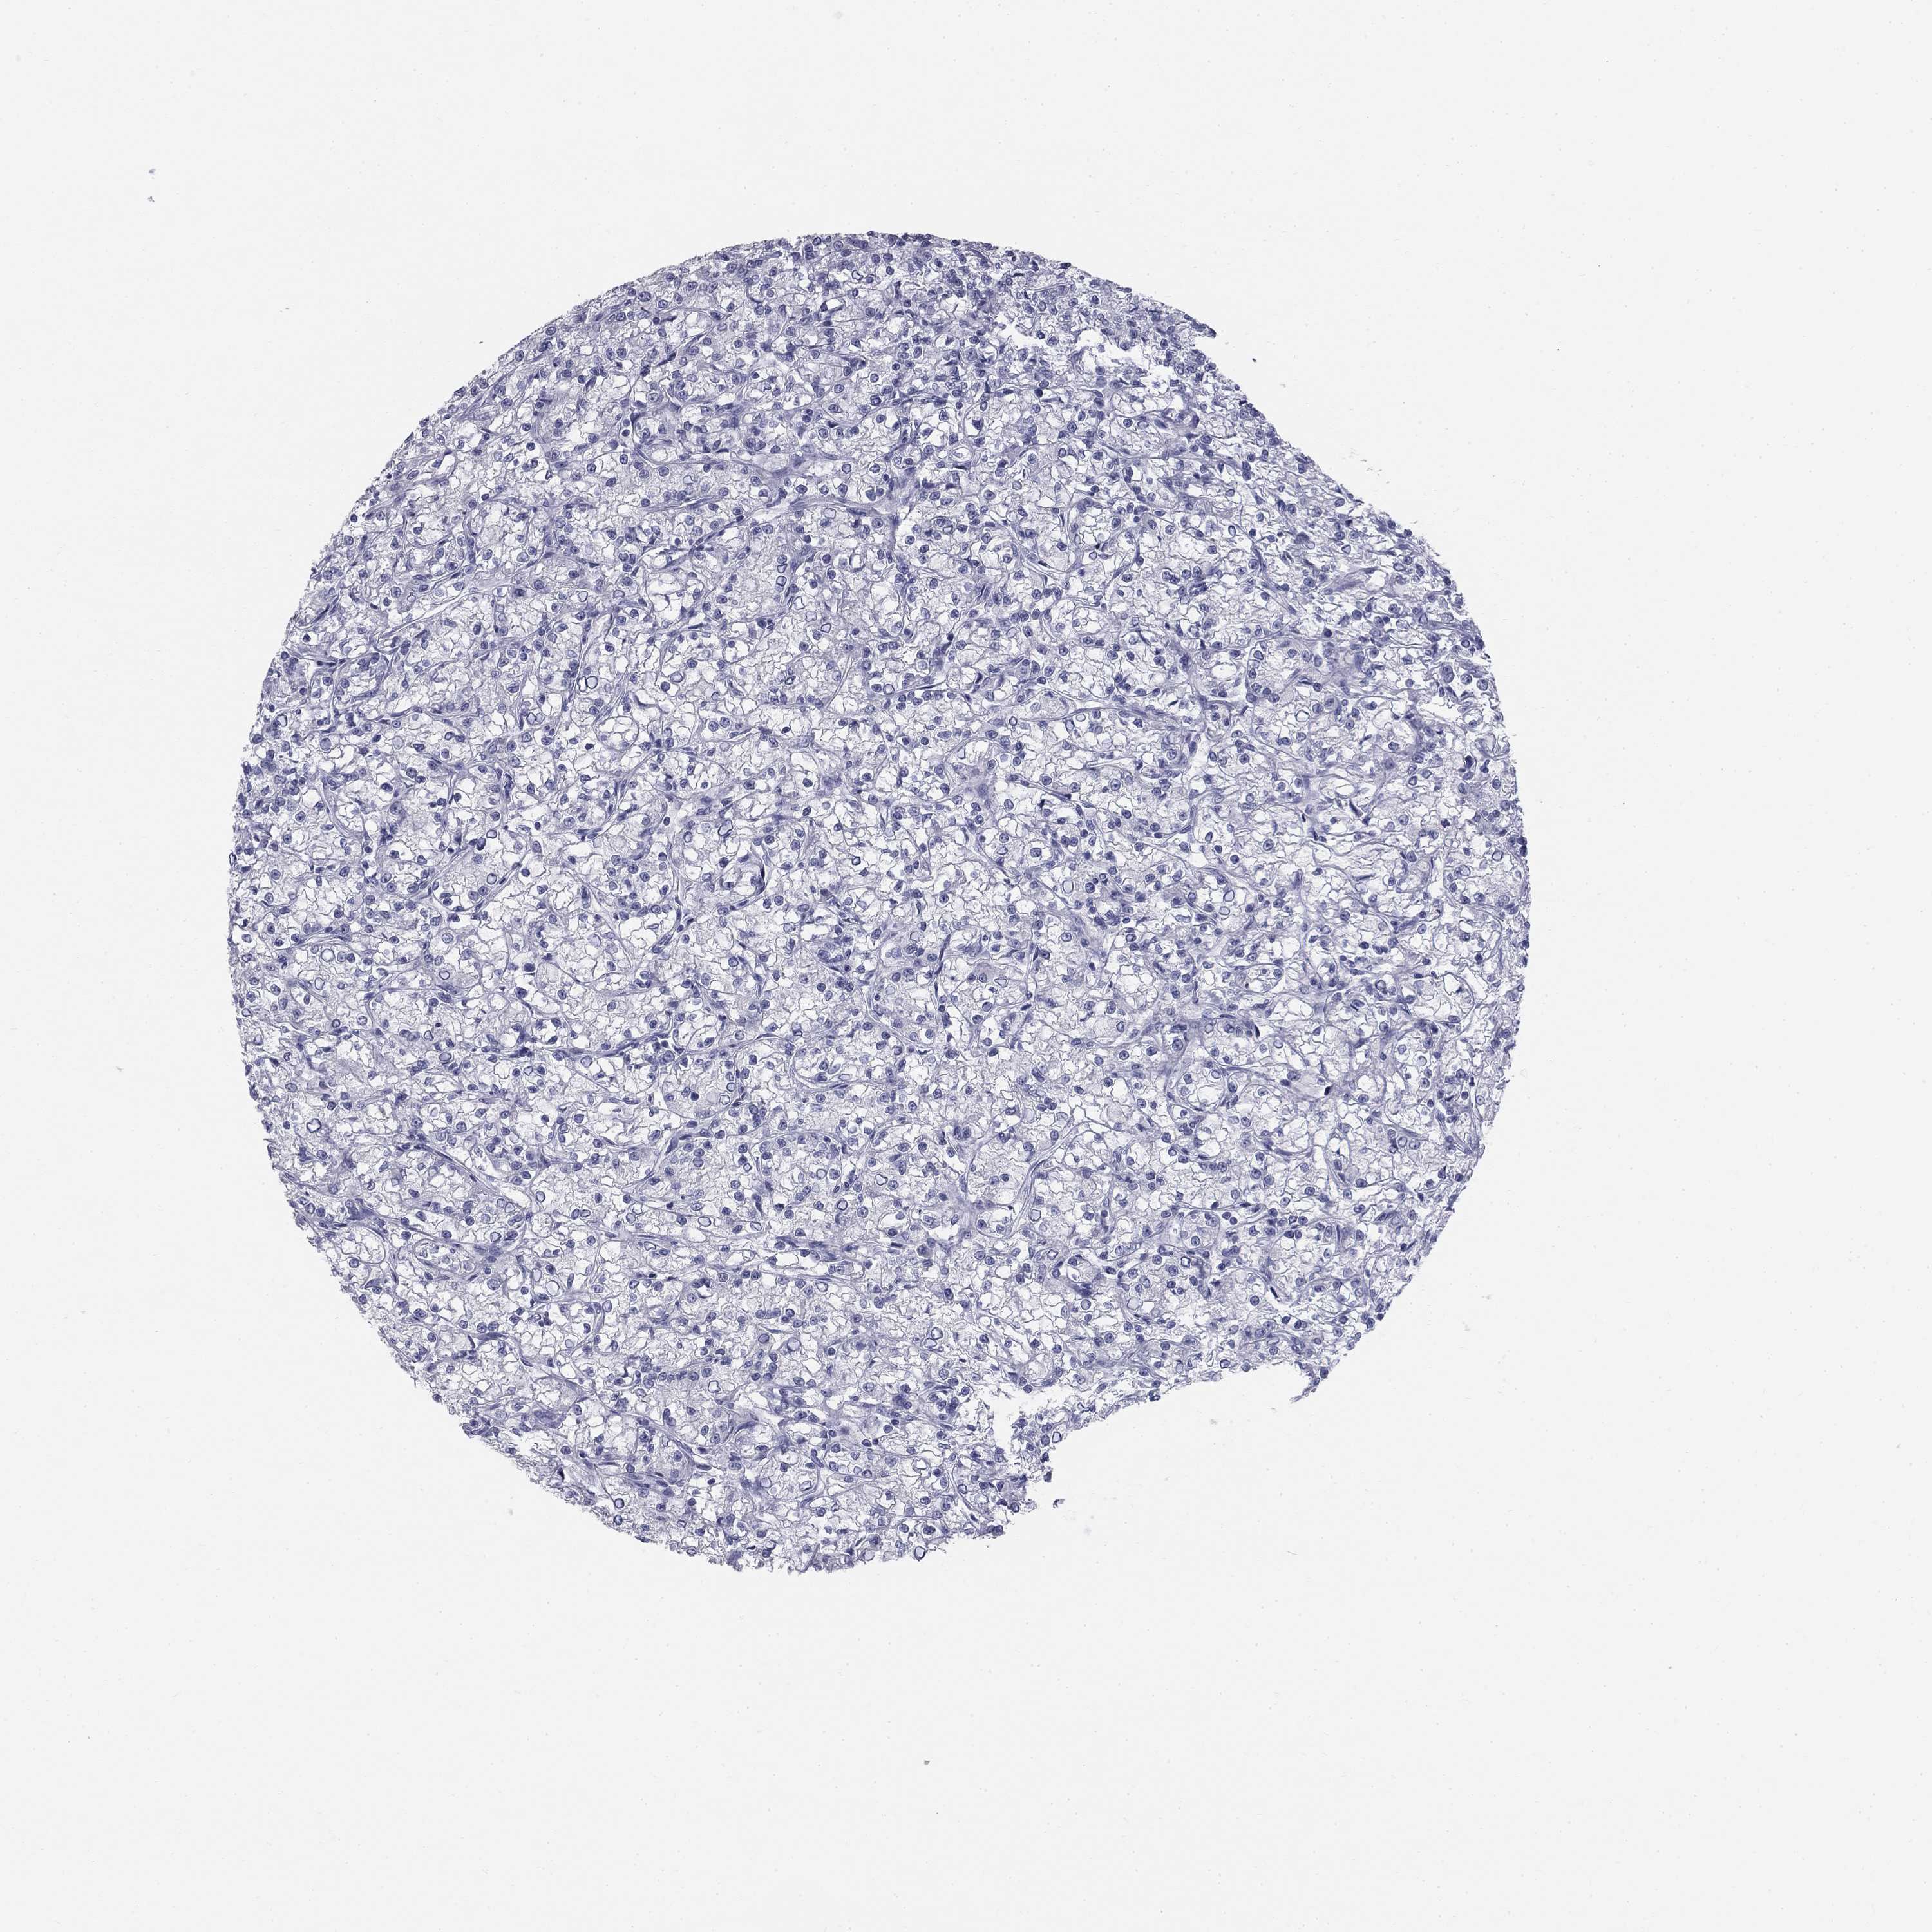

KIDNEY RENAL PAPILLARY CELL CARCINOMA (TCGA) - Interactive survival scatter ploti

The Survival Scatter plot shows the clinical status (i.e. dead or alive) for all individuals in the patient cohort, based on the same data that underlies the corresponding Kaplan-Meier plots. Patients that are alive at last time for follow-up are shown in blue and patients who have died during the study are shown in red.

The x-axis shows the expression levels (FPKM) of the investigated gene in the tumor tissue at the time of diagnosis. The y-axis shows the follow-up time after diagnosis (years). Both axes are complimented with kernel density curves demonstrating the data density over the axes. The top density plot shows the expression levels (FPKM) distribution among dead (red) and alive patients (blue). The right density plot shows the data density of the survived years of dead patients with high and low expression levels respectively, stratified using the cutoff indicated by the vertical dashed line through the Survival Scatter plot. This cutoff is automatically defined based on the FPKM cutoff that minimizes the p-score. The cutoff can be changed by dragging the vertical line or by entering a cutoff value in the square labeled "Current cut-off".

Under the Survival Scatter plot the p-score landscape (black curve; left axis) is shown together with dead median separation (red curve; right axis). Dead median separation is the difference in median mRNA expression between patients who have died with high and low expression, respectively. It is calculated as follows: median FPKM expression of dead patients with high expression - median FPKM expression of dead patients with low expression. This is intended to aid the user in visually exploring custom cutoffs and the associated p-scores and dead median separation.

Individual patient data is displayed and can be filtered by clicking on one or more of the category buttons on the top of the page. Categories describing expression level and patient information include: high, low, alive, dead, female, male and tumor stages. The scale of the x-axis can be toggled between linear and log-scale by clicking on the "x log" button. Mouse-over function shows TCGA ID, patient information and mRNA expression (FPKM) for each patient.

& Survival analysisi

Kaplan-Meier plots summarize results from analysis of correlation between mRNA expression level and patient survival. Patients were divided based on level of expression into one of the two groups "low" (under cut off) or "high" (over cut off). X-axis shows time for survival (years) and y-axis shows the probability of survival, where 1.0 corresponds to 100 percent.

SULT2B1 is not prognostic in Kidney Renal Papillary Cell Carcinoma (TCGA)

Best expression cut offi

Based on the FPKM value of each gene, patients were classified into two groups and association between prognosis (survival) and gene expression (FPKM) was examined. The best expression cut-off refers the FPKM value that yields maximal difference with regard to survival between the two groups at the lowest log-rank P-value. Best expression cut-off was selected based on survival analysis .

When clicking on this number, the vertical dashed line indicating cut-off, the interactive survival plot, and the Kaplan-Meier curve will be adjusted to show results based on the best expression cut-off.

: 1.65